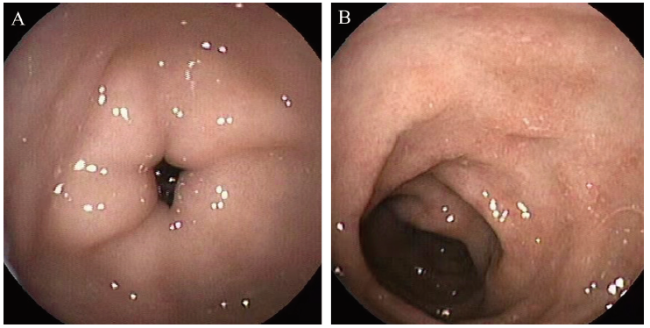

初步诊断:脓毒症;急性肠炎,坏死性小肠结肠炎可能;中度贫血。即予“头孢哌酮舒巴坦”抗感染、输注Ig,补液纠正水、电解质及酸碱平衡,肠外营养等治疗。入院第3日嘱母亲严格回避牛奶类饮食,继续母乳喂养并更换氨基酸配方混合喂养,第4日体温正常,未再呕吐,腹泻次数减至3 ~ 4次/日,未见黏液及脓血便,腹胀缓解。复查血常规白细胞 14.94×109 /L,中性粒细胞7.25×109 /L,血红蛋白100 g/L,血小板609×109 /L,CRP 25.9 mg/L。粪常规未见异常,隐血(-)。予停用头孢哌酮舒巴坦抗感染,第7日复查血常规白细胞 9.76×109/L,CRP 52 mg/L,血红蛋白 98 g/L,停肠外营养。第11日体质量增至3.8 kg。但第14日患儿再次剧烈呕吐,伴有发热、腹泻,便中见少许血丝,且精神差,呼吸促,眼眶凹陷,尿量少,血压68/36 mm Hg,立即予扩容补液、纠酸。复查粪便常规示白细胞6 ~ 10个/高倍视野,粪便隐血(+);血常规示白细胞24.02×109/L,中性粒细胞21.89×109/L, 血小板 414×109/L,CRP 17.2 mg/L;追问病史,母亲前一日有进食125 mL酸奶史,故嘱停母乳,仅予氨基酸配方奶粉喂养,1 d后体温正常,未再呕吐,腹泻好转,无血便。复查粪便隐血(-)。血常规示白细胞 8.67×109 /L,中性粒细胞4.1×109/L,血小板496×109/L,CRP 0.3 mg/L。患儿因病程迁延,营养不良行肠镜(奥林巴斯)检查,镜下表现为十二指肠球部黏膜肿胀,乙状结肠、降结肠黏膜散在浅凹溃疡灶(图2)。患儿氨基酸配方奶粉渐增至100 mL/3 h,无呕吐,无腹胀,黄糊状便2 ~ 3次/日,共住院28 d出院,体质量达4.3 kg。最后诊断:FPIES(慢性型,重度);营养不良(中度,消瘦型);中度贫血。随访至18月龄时更换普通牛奶成功,期间已添加蔬菜、水果并逐渐添加米粉、豆类等辅食。目前身长、体质量在同龄儿、同性别参照人群均值的2个标准差之内。

图2 例2 FPIES患儿肠镜图

注:A为乙状结肠红斑、溃疡;B为降结肠溃疡。

实验室检查中性粒细胞和(或)血小板增多支持诊断FPIES,但只存在于约50%的病例中,中性粒细胞可与细菌性败血症一样高,而且血液中性粒细胞在摄入致敏食物后6 h左右达到峰值[8]。此外观察到CRP在急性FPIES或OFC后的升高,其升高水平和反应的严重度相关。例2入院时CRP 207.6 mg/L,入院后嘱母亲回避牛奶相关食品联合氨基酸配方喂养症状缓解,复查CRP 5.2 mg/dL,但11 d后母亲自行进食酸奶后,患儿再次频繁呕吐、脱水,复测白细胞和中性粒细胞均明显上升,CRP升至17.2 mg/L,亦与报道一致。例2因病程迁延,营养不良行内镜检查,但是FPIES的内镜表现没有特异性,内镜检查不建议作为常规检查[9]